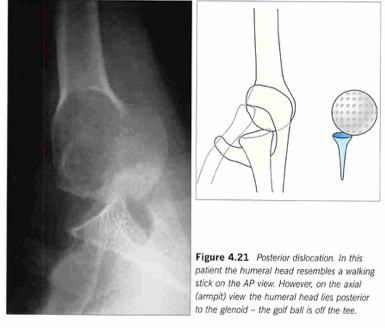

病歴と診察所見からまずはいつもの肩関節のレントゲン、AP (anteroposterior)viewを撮影しますが、APviewではパッと見た感じ正常っぽく見えます。完全に正常と変わらないこともあります。

これが初診時に見逃してしまうポイントです。

しかしAPviewでも後方脱臼に特徴的なサインがいくつかあります。6~9),11)

・Lightbulb sign(ice cream corn sign):

上腕骨頭が内旋により電球のように左右対称に見えます。(正常ではやや外旋位なのでAPviewで大結節のノッチがゴルフのクラブヘッドのような杖のような形ですね)。ただ、これは後方脱臼によるものではなく上腕骨の内旋によるものであり、肩に痛みのある患者さんはしばしば上肢を内旋して動かさない為、後方脱臼以外でも見られることがあります。

・The ‘rim sign’:

関節窩(前面)と上腕骨頭の距離が広がります。>6mmは’positive rim sign’といってより疑わしい所見です。似たようなもので関節窩の前面が空っぽに見えるThe vacant glenoid signというのもあります。

trans-scapular view(Y-view)ではより後方脱臼の所見がわかりやすくなります。

関節窩の後ろに上腕骨頭が位置します。(正常では烏口突起、肩峰、肩甲骨板の作るY字の中央に関節窩があるので、上腕骨頭もそこに位置します。)

その場合はAxillary viewが理想的な viewとなります。4)

Axillary viewは肩関節を70~90度外転し、腋窩から45度の角度で撮影するviewです。通常、肩のレントゲンを撮る際は、あまり選択しないviewですが、後方脱臼を診断するときには最も役立つと言われます。